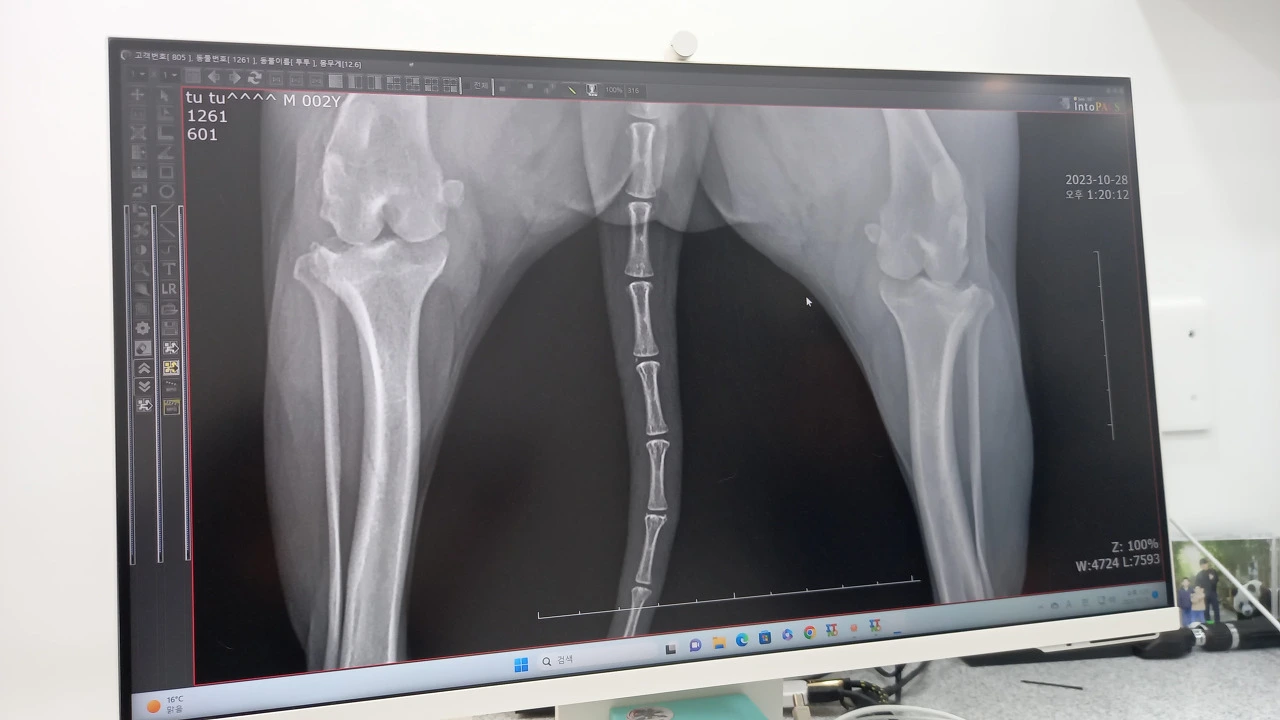

다음 날 오전, 서둘러 병원에 갔다. 엑스레이를 찍어보니 슬개골 탈구가 된 상태였고 인대도 끊어졌을 가능성이 높다고 했다. 엑스레이엔 인대가 보이지 않았다. 또 철렁! 엑스레이 사진은 의학적 지식이 없는 사람이 보아도 알 수 있을 만큼 상황이 나빠보였다. 뼈와 뼈 사이가 간격 없이 바짝 붙어 있고 아래 뼈는 휘어져 있었다. 수의사는 그동안 통증이 심했을 거라며 당장 수술을 해야 한다고 했다. 눈물이 쏟아졌다. 겁에 질려 덜덜 떠는 투투를 끌어안고 나 또한 겁이 나 울었다.

휘어지고 맞닿아 있는 뼈

치료에 필요한 수술과 처치에 동의하고 그 후의 결과에 대해서 법적인 다툼을 하지 않는다는 수술 동의서에 사인을 한 후 투투는 수술을 했다. 인대 상태를 걱정하며 들어간 수의사가 도중에 나와서 걱정한 대로 양쪽 인대가 다 끊어진 상태이니 슬개골 수술과 함께 인대 재건 수술도 해야 한다고 했다. 의사의 말이 귓가에서 윙윙댔고 눈물이 쏟아졌다. 수술은 2시간 30분이 걸렸다. 수술 후 다시 찍은 엑스레이엔 휘어진 다리뼈를 교정하느라 박은 핀이 두 개씩 하얗게 박혀있고 뼈 사이의 간격도 처음 사진과는 다르게 벌어져 있었다. 관절 바로 아래엔 작은 구멍도 하나씩 나 있었는데 인대를 고정해 놓기 위해 뚫은 구멍이라고 했다. 그 사이로 인대를 통과시켜 슬개골 뒤쪽에 핀으로 박아 고정했단다. 핀을 박은 것도 뼈에 구멍을 뚫은 것도 그저 놀랍고 무서웠다.